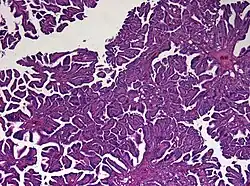

Histologie des Plexuspapilloms mit typischen papillären Strukturen. Hämatoxylin-Eosin gefärbtes Schnittpräparat. Originalvergrößerung 1:40

Bei höherer Vergrößerung sind die relativ einheitlich geformten (monomorphen) Zellkerne und die fehlende mitotische Aktivität gut erkennbar. Hämatoxylin-Eosin gefärbtes Schnittpräparat. Originalvergrößerung 1:400

Das feingewebliche Bild ähnelt mit Ausbildung papillärer Strukturen weitgehend dem des normalen Plexus choroideus. Tumoren, die atypische histologische Eigenschaften (insbesondere eine erhöhte mitotische Aktivität) aufweisen, werden als atypisches Plexuspapillom bezeichnet.[5]

Diagnostisch hilfreich ist der immunhistochemische Nachweis einer Expression des Zytokeratins CK7, Vimentin und S-100. Schwierigkeiten kann bei Erwachsenen die Abgrenzung gegenüber Hirnmetastasen bereiten. Der Nachweis einer Expression von plexustumor-spezifischen Markern kann dazu beitragen, die Verdachtsdiagnose eines Plexuspapilloms zu erhärten.[6][7]